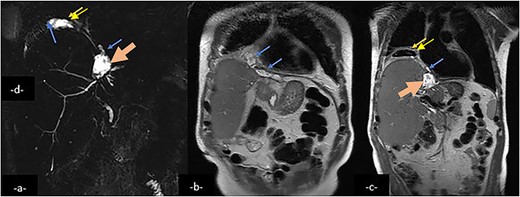

Magnetic resonance cholangio pancreatography (MRCP) in Radial T2 SSFSE sequence and coronal T2 showing a collection (large arrow) in the left hepatic lobe, subphrenic collection (arrow) and right pleural collection (double arrow) containing air and communicating with airways.

MRI, including MRC, offers the advantage of multiplanar imaging capabilities and can effectively demonstrate distal biliary obstruction. However, it has limitations in visualizing nondistended ducts, which is often the case with BBF [11].